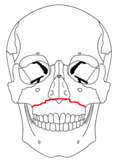

- Le Fort I fracture (horizontal), otherwise known as a floating palate, may result from a force of injury directed low on the maxillary alveolar rim, or upper dental row, in a downward direction. The key component of these fractures, in addition to pterygoid plate involvement, is involvement of the lateral bony margin of the nasal opening. They also involve the medial and lateral buttresses, or walls, of the maxillary sinus, traveling through the face just above the alveolar ridge of the upper dental row. At the midline, the inferior nasal septum is involved. Historically, it has also been referred to as a Guérin fracture, although this name is less commonly used in practice.

- Le Fort II fracture (pyramidal) may result from a blow to the lower or mid maxilla. The key component of these fractures beyond the pterygoid plate fractures is involvement of inferior orbital rim. When viewed from the front, the fracture is classically shaped like a pyramid. It extends from the nasal bridge at or below the nasofrontal suture through the superior medial wall of the maxilla, inferolaterally through the lacrimal bones which contain the tear ducts, and inferior orbital floor through or near the infraorbital foramen.